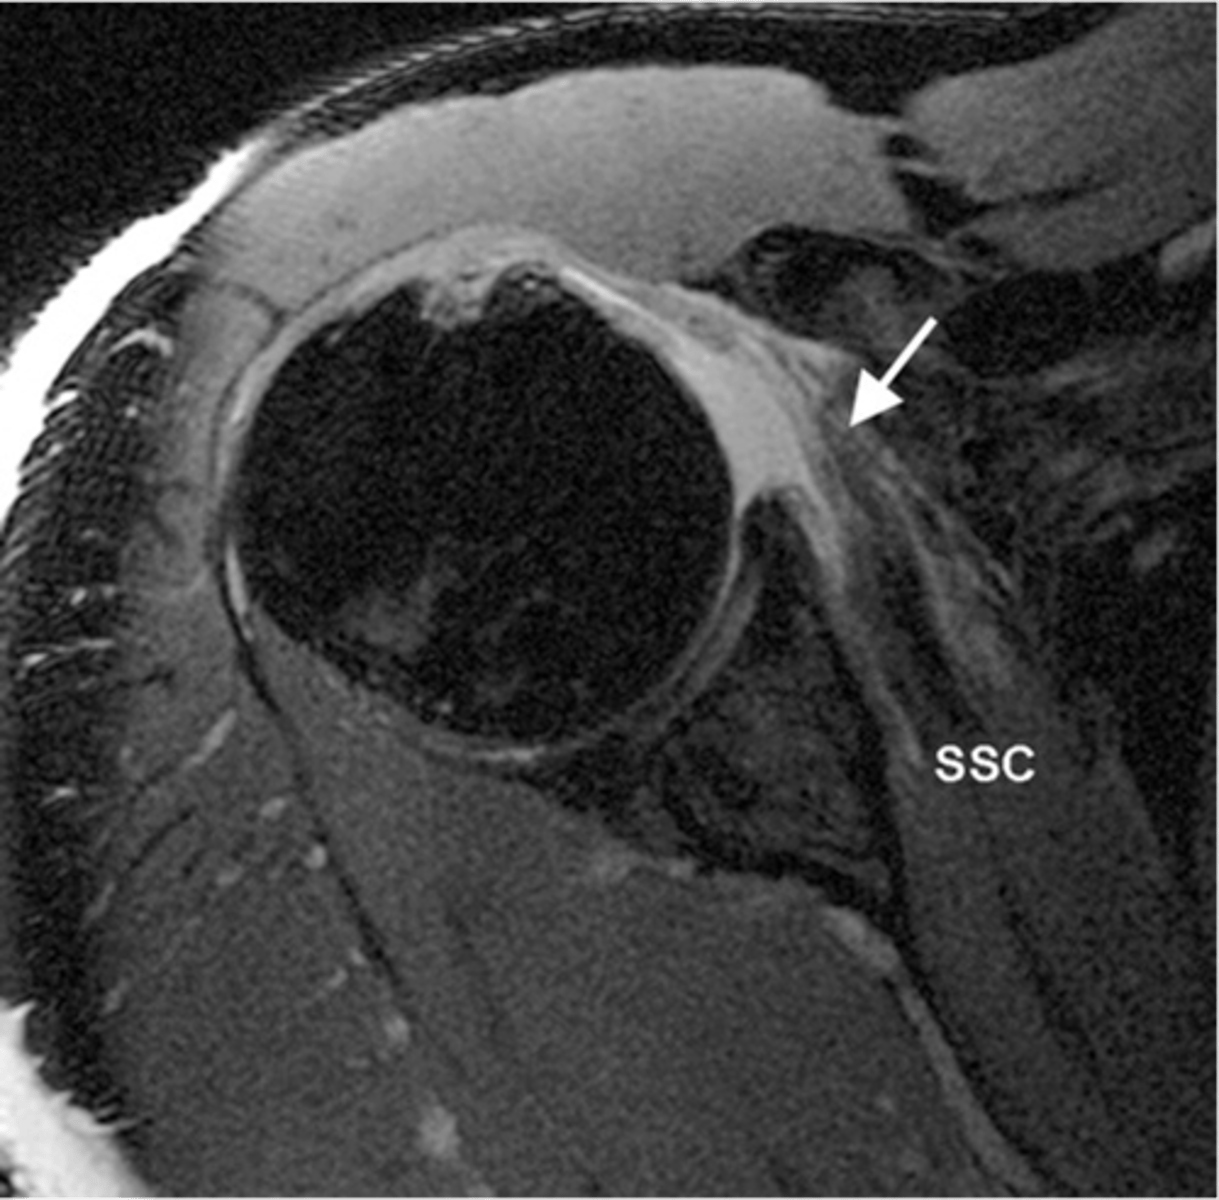

Axial view of the shoulder w/ atrophy of the subscapularis -- fat is depicted in white in the middle of the muscle, which is a tell-tale sign of disuse, atrophy, neurological impairments, or tendon tears

What is this image depicting? How do you know?